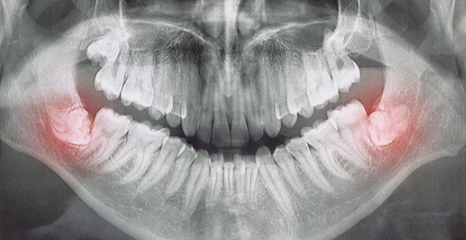

- X-ray 검사: 매복 상태 확인.

매복 사랑니는 턱뼈 안에서 완전히 나오지 못하거나 비정상적인 각도로 자란 사랑니를 말합니다. 이런 사랑니는 주변 치아를 밀거나 잇몸 염증, 통증 등을 유발할 수 있어 발치가 필요합니다.